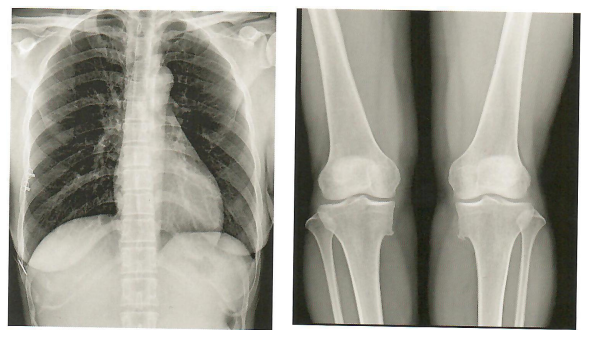

精准诊断,卓越超群的影像质量,毫秒抓拍,满足多种临床诊断需求。

胸部摄影 四肢摄影